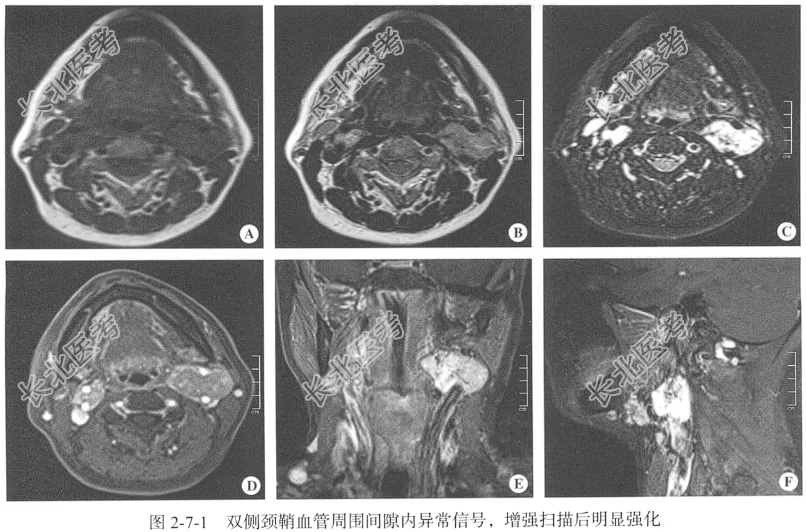

查体:颈部对称,无抵抗感,无强直,无压痛,左侧颌下区可触及3cm×3cm肿块,质韧,无压痛,与周围组织无粘连,无活动受限,颈动脉搏动正常,颈静脉无怒张,肝颈静脉回流征阴性,气管居中,双侧甲状腺无肿大,未触及震颤,无血管杂音。颈部MRI检查:仰卧位,横断位扫描,包括T₁WI、T₂WI及T₂脂肪抑制序列,扫描范围:寰椎至第5颈椎椎体间,扫描层厚为3.0mm;辅以矢状位T₂WI、冠状位T₂脂肪抑制序列平扫后行横断位、冠状位及矢状位增强扫描。

见图2-7-1。